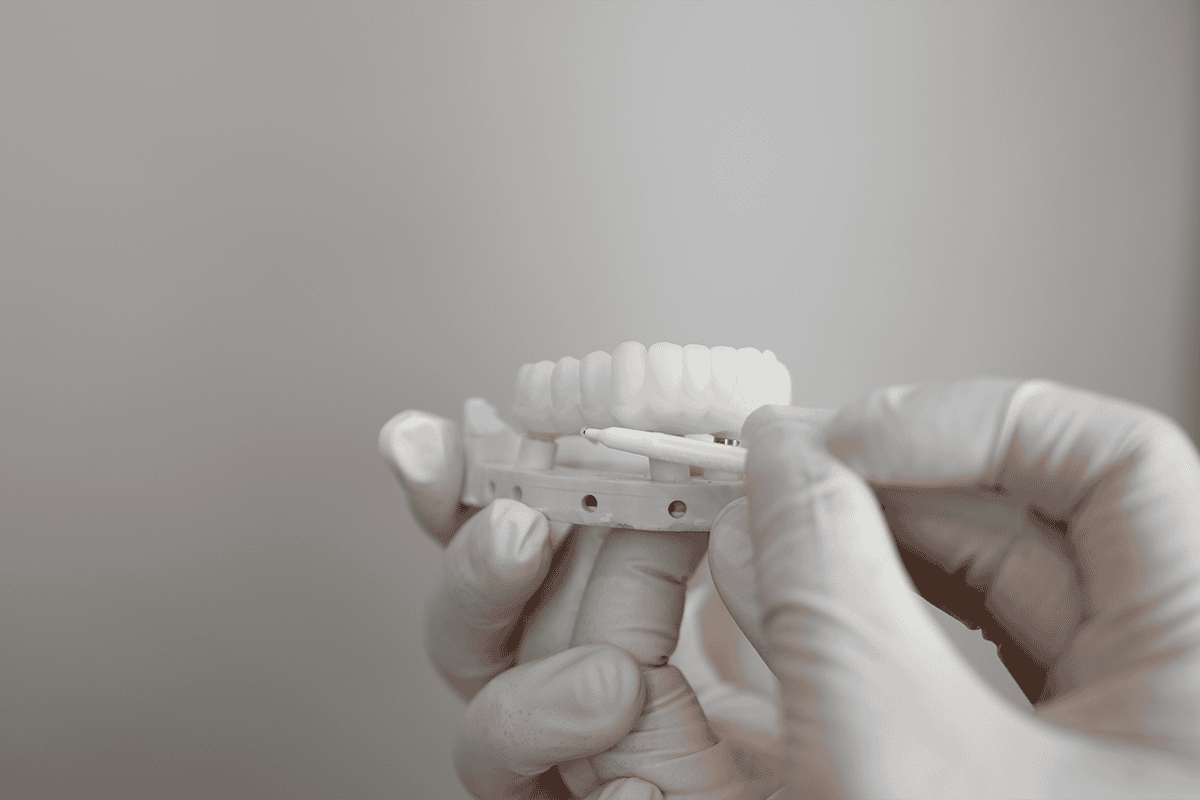

All-On-4 dental implants

At our Perth clinic, single dental implants or All-On-4 implants are available, depending on your condition. Our innovative All-On-4 treatment is a high-quality, permanent alternative to dentures. This incredibly effective solution to replacing terminal or missing teeth gives you back full functionality, so that you can enjoy your favourite foods again.

Porcelain veneers

Advanced Dental Artistry’s porcelain veneers are made using the highest quality materials and innovative technology to create a natural looking, more uniform smile. Each of our ultra-thin porcelain veneers are hand-crafted to ensure they are completely customised to your face. Offering the optimal solution to stained, chipped or cracked teeth, our porcelain veneers are seamlessly bonded to your natural teeth, helping to restore damage and give you a natural look and feel.

Full mouth reconstruction

Ideal for those that don’t require full teeth replacement, our full mouth reconstruction service is a highly tailored process that uses a combination of hand-crafted porcelain veneers and dental implants. The result is a professionally restored smile that promotes improved oral health.